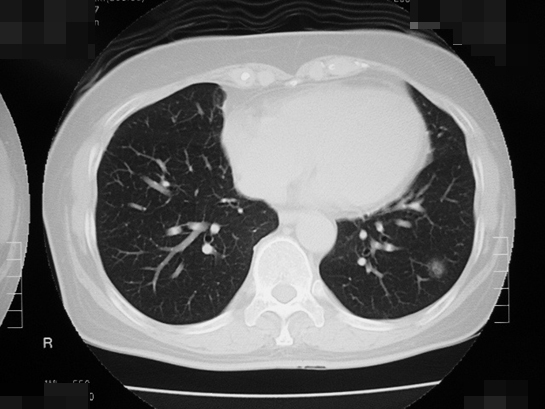

近年増加しているタバコを吸わない女性に多い「肺腺がん」とは、ごく早期のすりガラス陰影といわれるCT検査でしか見えないようながんで、周辺部の影が淡く、直径1.5cm以下であれば、日本肺癌学会のガイドラインでは経過観察でよいとされています。比較的おとなしいがんで、1cm以下のすりガラス状の肺腺がんで女性の場合は、5年後にがんが大きくなっている人は1割程度で、残りの9割の人は大きくならないで、なかには一生そのままの状態の人もいたとの報告もあります。経過観察して、たとえば5年たって大きくなったならその時に、肺を部分的に切除する手術をすればよく、術後の抗がん剤治療も必要ありません。ただ、肺の正常な部分とがん化したすりガラス状に映る影との境界線がはっきりしていたり、影の中にくっきりした部分が広がっている場合は早期ではない可能性があり、注意が必要です。さらに、多発しやすいという性質もあります。

バコを吸わない女性に多い肺がんのCT画像